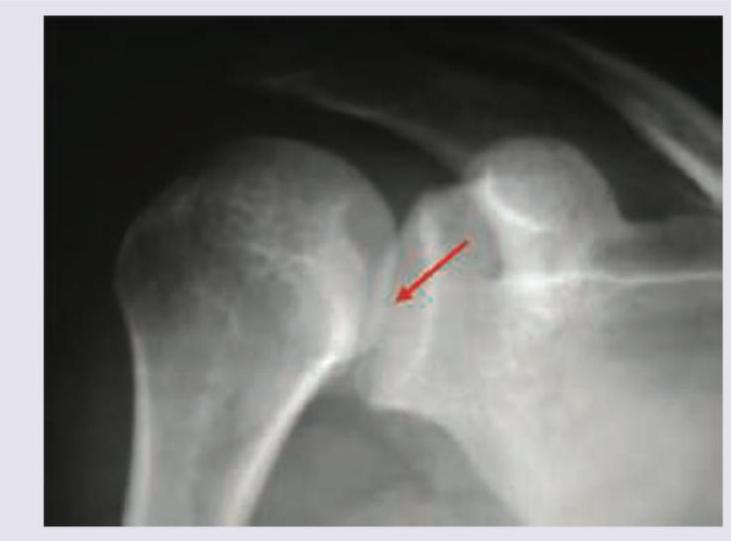

Explanation: ***Hill-Sachs lesion*** - The image shows a **compression fracture** or **dent** in the **posterolateral aspect of the humeral head**. - This lesion is characteristic of an **anterior shoulder dislocation**, occurring when the humeral head impacts the anterior glenoid rim. *Bankart lesion* - A Bankart lesion involves an avulsion of the **anterior inferior labrum** from the glenoid rim. - It is often seen in conjunction with a Hill-Sachs lesion following an anterior shoulder dislocation but refers to damage to the labrum, not the humeral head itself. *Reverse Hill-Sachs lesion* - A reverse Hill-Sachs lesion is a compression fracture on the **anteromedial aspect of the humeral head**. - This lesion is typically associated with a **posterior shoulder dislocation**, which is the opposite mechanism to the injury suggested by the visualized humeral head defect. *Posterior Bankart lesion* - A posterior Bankart lesion involves an avulsion of the **posterior inferior labrum** from the glenoid rim. - This lesion is associated with **posterior shoulder dislocations** and relates to labral injury, not the bony defect on the humeral head shown.